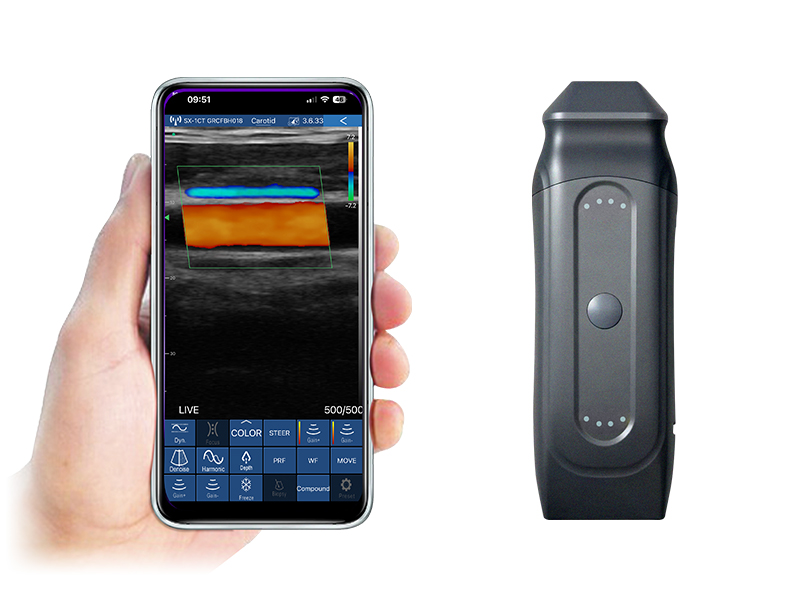

8L linear palm doppler ultrasound scanner

8N linear palm doppler ultrasound scanner

8H linear palm doppler ultrasound scanner

8S linear palm doppler ultrasound scanner

6L/6P linear palm doppler ultrasound scanner

6N linear palm doppler ultrasound scanner

5L linear palm doppler ultrasound scanner

5P UHF linear palm doppler ultrasound scanner

5W ultra-wide linear palm doppler ultrasound scanner

4L linear palm doppler ultrasound scanner

3L linear palm doppler ultrasound scanner

5L linear palm B/W ultrasound scanner

3L linear palm B/W ultrasound scanner